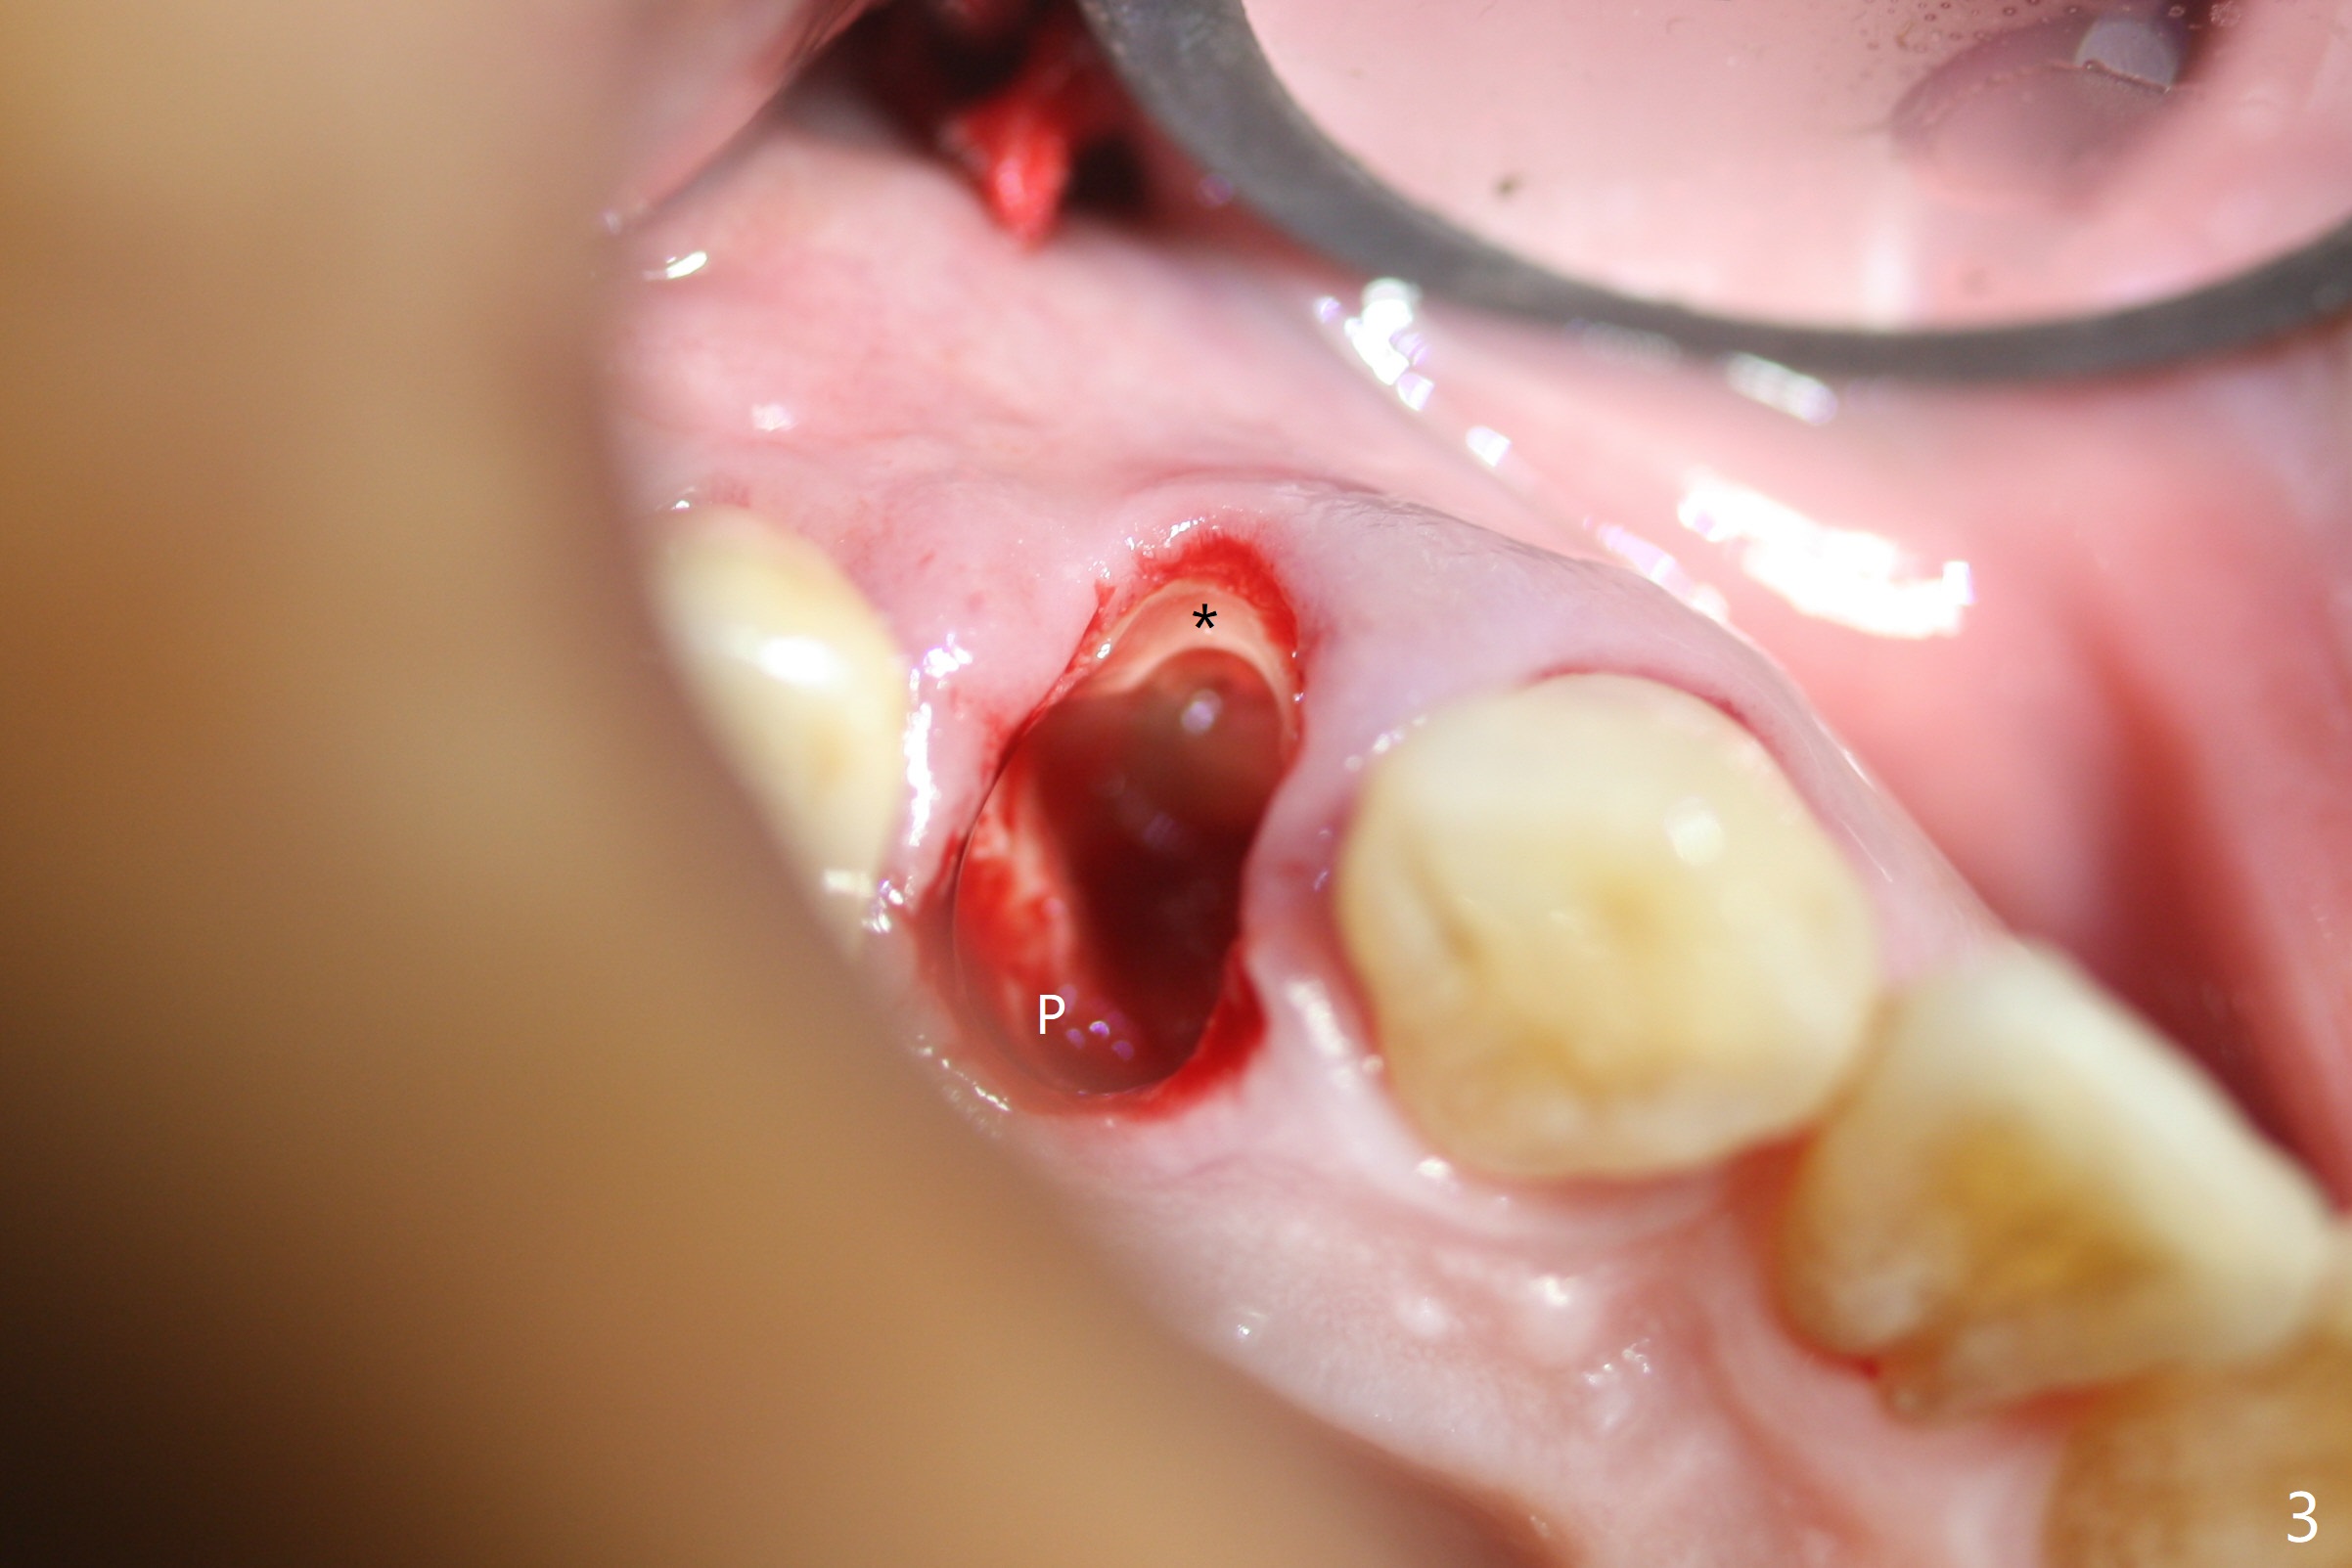

The buccal plate is normal at the tooth #5 (Fig.1) with the loose palatal fragment (Fig.2 P). Extraction leads to root fracture. Sectioning removes the palatal portion of the root and keeps the buccal semilunar piece (Fig.3 *); the mesiopalatal plate is resorbed (P). Initial osteotomy is off (Fig.4 (R: remaining root)). Redirection improves the trajectory (Fig.5). With the 2nd redirection (Fig.6 (4.5 mm tap)), a 4.5x12 mm implant is placed with 50 Ncm and sinus lift (Fig.7 black *); bone graft is placed with emphasis on the palatal defect (white *). As usual, an immediate provisional is fabricated. In fact the abutment may be not completely seated because of contact with the mesial crest. Prepare anesthetic and 5.5 mm profile drill. Take parallel BW or PA. Take occlusal photos to show no buccal or mesiopalatal atrophy. After 5.5 mm profile drill 11 months postop, the abutment has no contact with the mesial crest (Fig.8 <). Since the proximal contact between #3 and 4 is light with food impaction, the provisional at #5 is fabricated with tight distal contact. When the patient returns for final crown cementation (Fig.9), the food impaction is minimal between #3 and 4. The distal black triangle (Fig.10 *) and exposure of the abutment margin (^) are partially related to provisional fabrication and should dissolve over time considering socket shield.